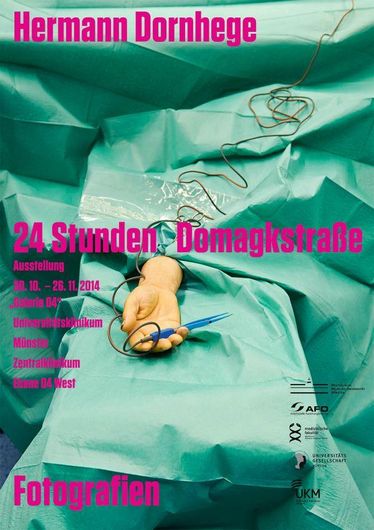

30.10.2014

- 26.11.2014

Domagk-Jahr 2014: Fotoausstellung 24 Stunden Domagkstraße"

Domagk-Jahr 2014: Fotoausstellung 24 Stunden Domagkstraße"